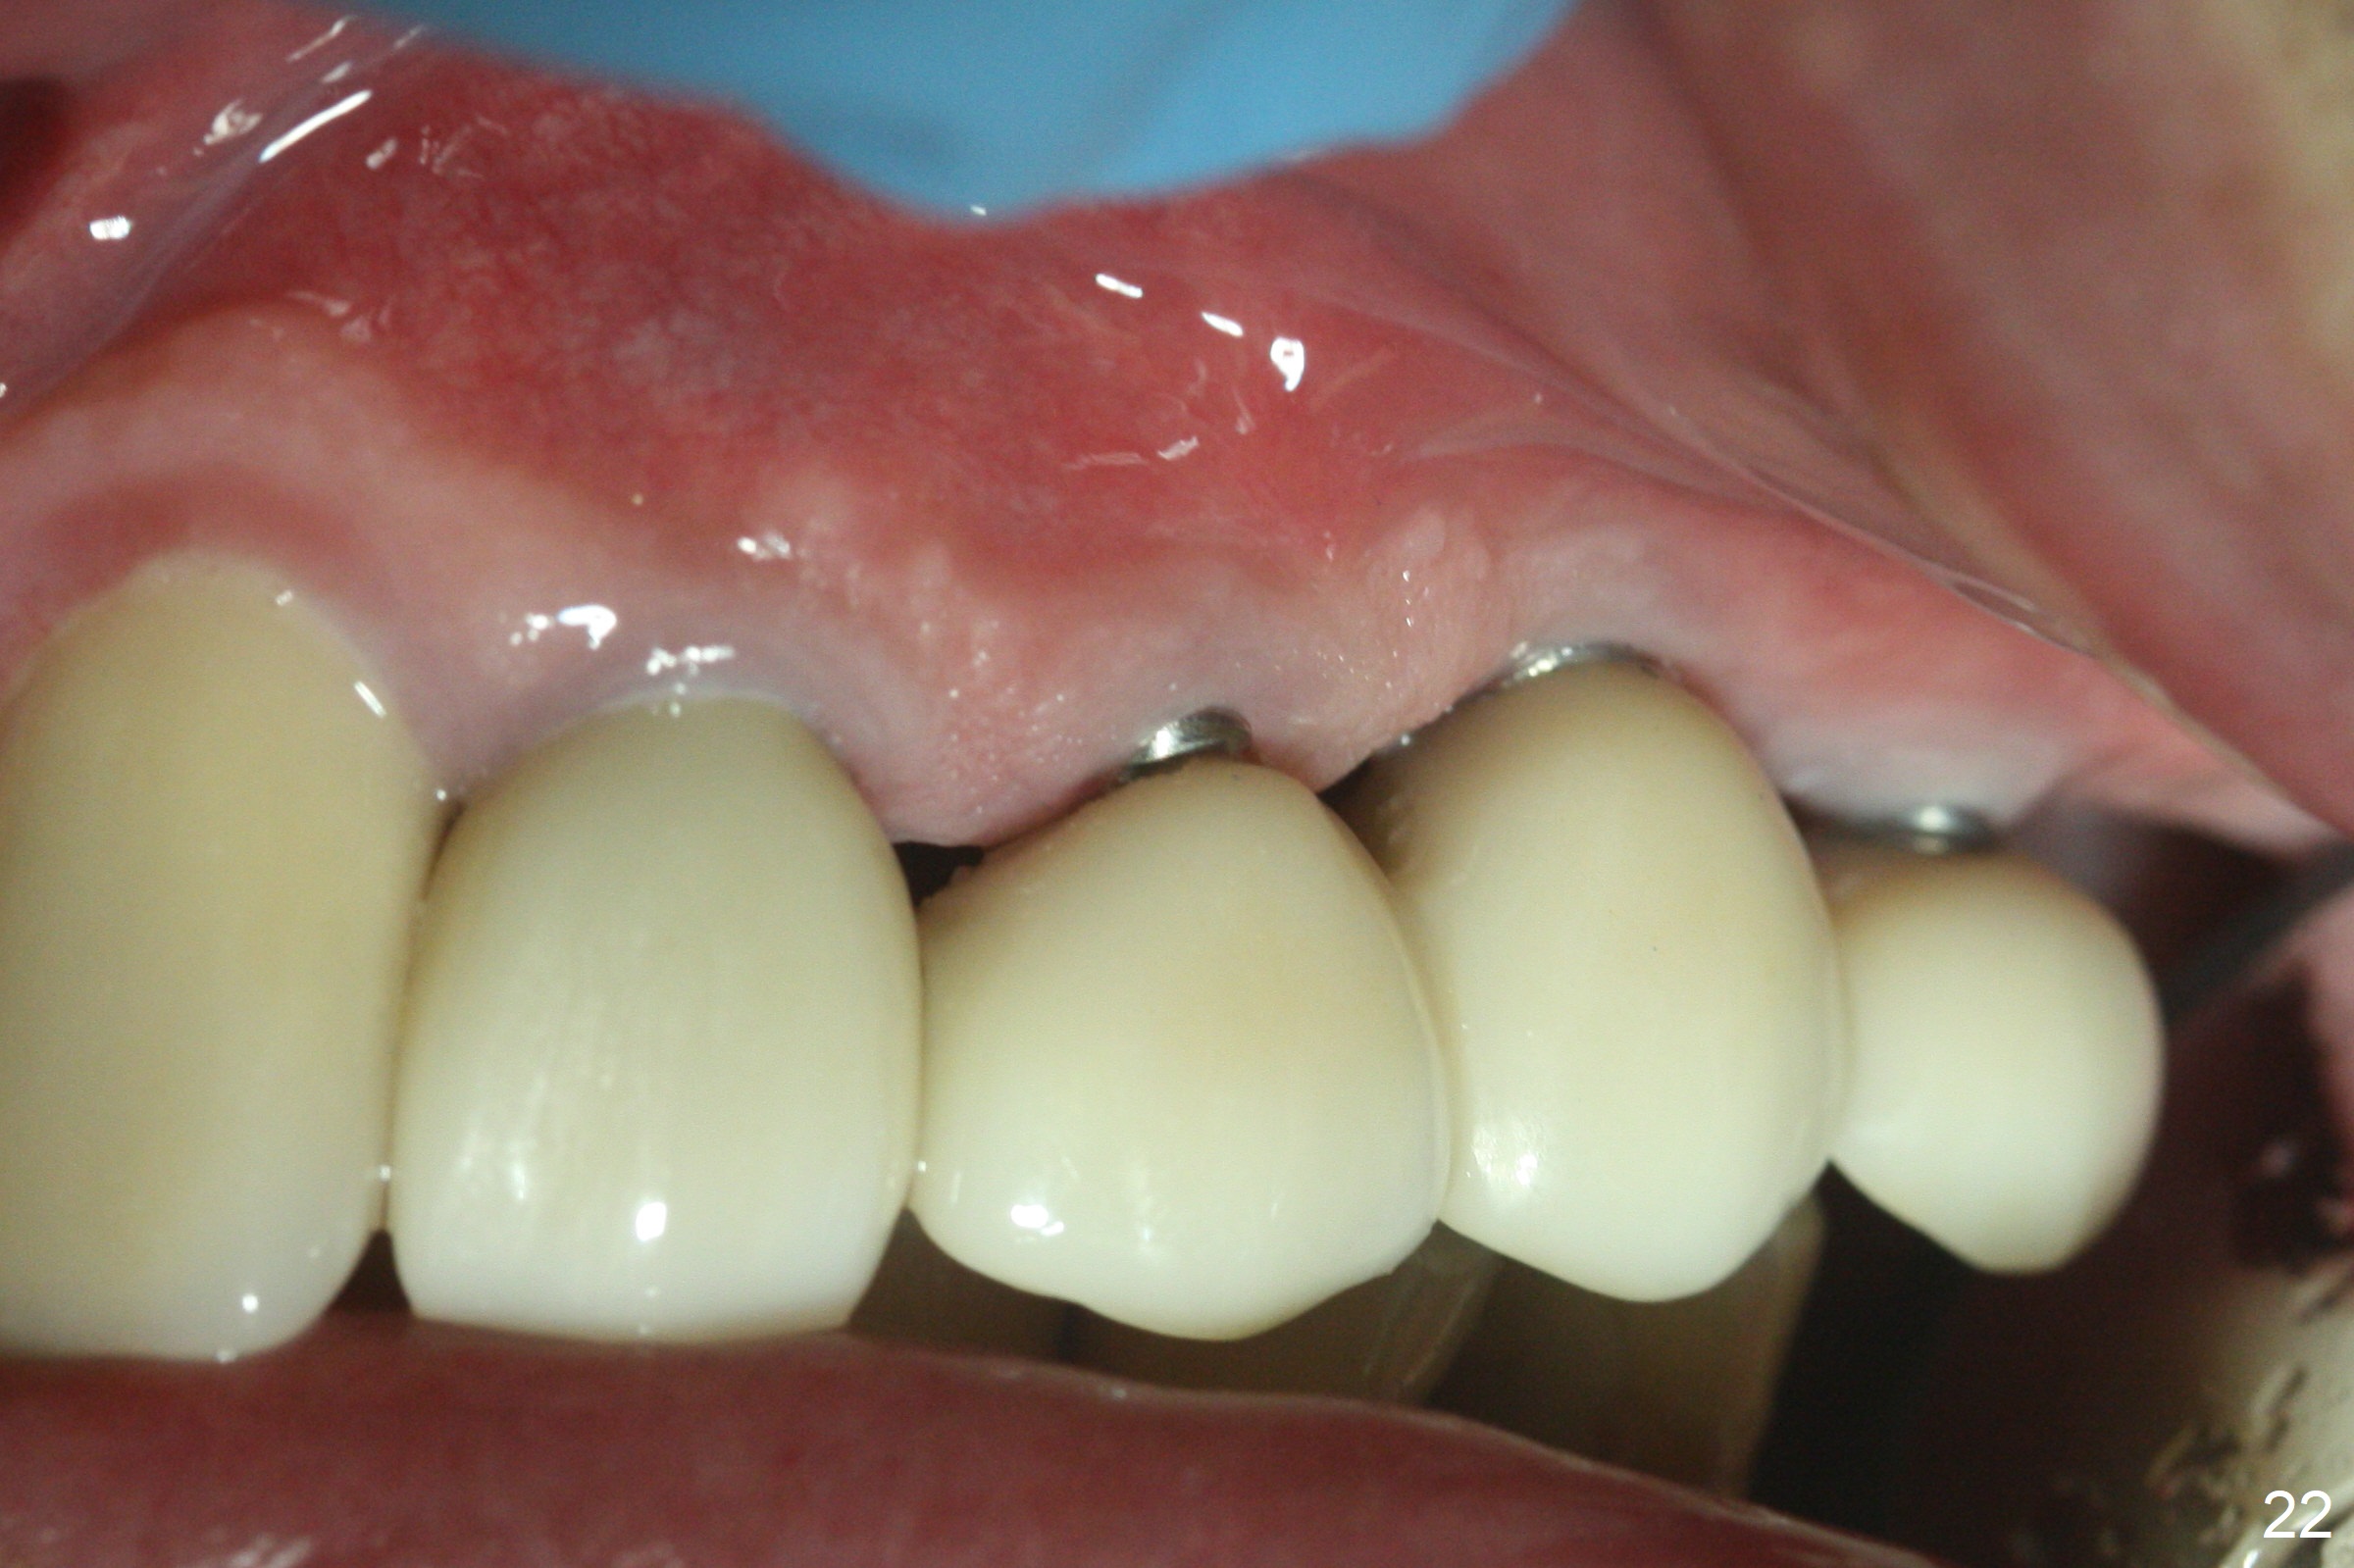

Six months post cementation, the tooth #9 becomes symptomatic. Is it possible that the implant at #10 is too close to the root of #9? It is asymptomatic after pulpotomy, but the tooth fractures equi/supragingivally. Two PAs taken while RCT show osteointegration at #10-12 (Fig.18,19). While the bone density increases at #10 regular implant, there is minimal bone loss around the 1-piece implants 13 months post cementation (18 months postop, Fig.20,21). The gingiva remains healthy 19 months post cementation (Fig.22). 76岁病人突然打电话说一个植牙牙冠松动,其实9号牙(自然牙)折裂,6,10-13号牙植牙好像没有骨质吸收(图二十三至二十五),10-13牙位牙龈健康(图二十六,行使功能五年)。9号牙牙冠重新粘固后,显示前牙深覆合,深覆盖(图二十七,二十八)。如果再次脱落需要植牙,选择一段式有助于植入和修复,因为植体和基台直径小。两段式植牙相对基台直径至少4,或者4.5毫米,前牙修复显得笨重。由于9,10牙根和植体接近,9号牙植体需要偏小而长,3x14或者15毫米(图二十九)。